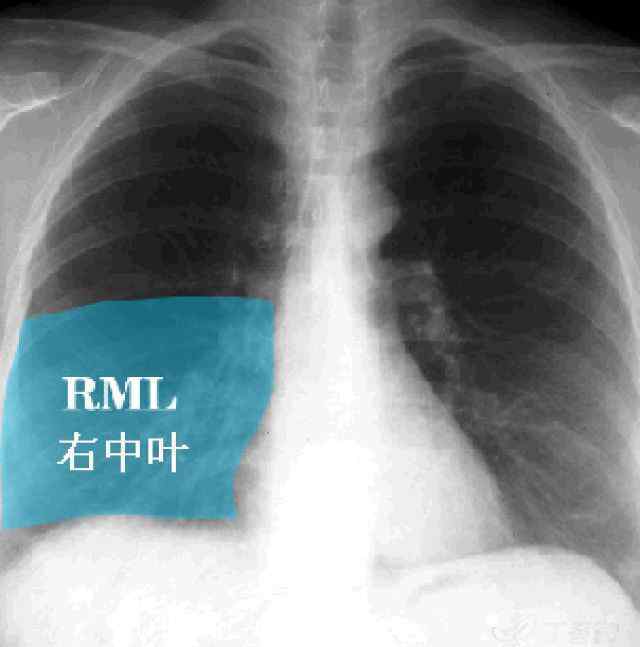

右肺中叶

●轮廓征的应用:如用于大叶性肺炎的定位。正投影片——右上纵隔对应右上叶,右心缘对应右中叶或右下叶基段,右膈面对应右下叶,左上纵隔对应左上叶,左心缘对应左上叶舌段,左膈面或降主动脉对应左下叶。

●侧位片也适用:心脏后缘或左膈后部对应左下叶,右膈前部对应右中叶,右膈后部对应右下叶。

看了轮廓征的解释,病例2的诊断准备出来了吗?右肺中叶大叶性肺炎。